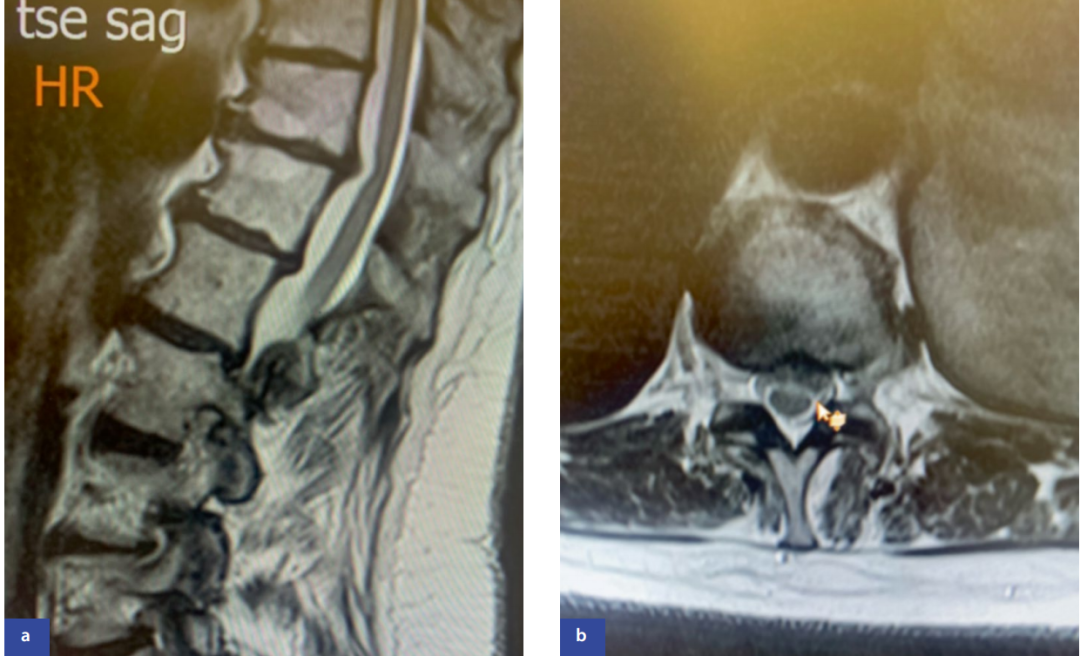

症状以脊髓病为主(下肢无力、步态异常、感觉障碍),可伴膀胱功能障碍。疼痛部位多样:上胸椎突出模拟心绞痛,中胸椎突出类似胃病,下胸椎突出常为影像学偶然发现(图4)。

图4:腰椎磁共振成像矢状位(a)和轴位(b)显示胸10/胸11节段左侧中外侧椎间盘突出(箭头标示)